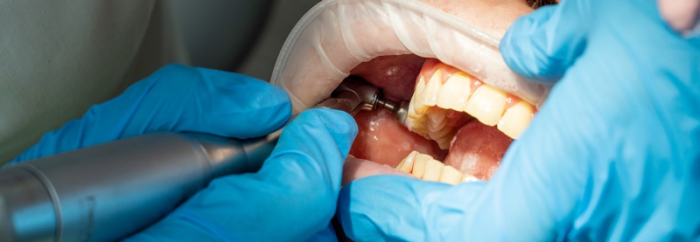

강남새로치과에서는 잇몸 속에 치은 연하를

쌓이게 만드는 구강 내의 유해 세균과

치아 겉에 붙은 치태, 치석을 체계적이고

효율적으로 제거하는 무통 스케일링을 통해

잇몸내려앉음을 철저히 예방하고 있는데요.